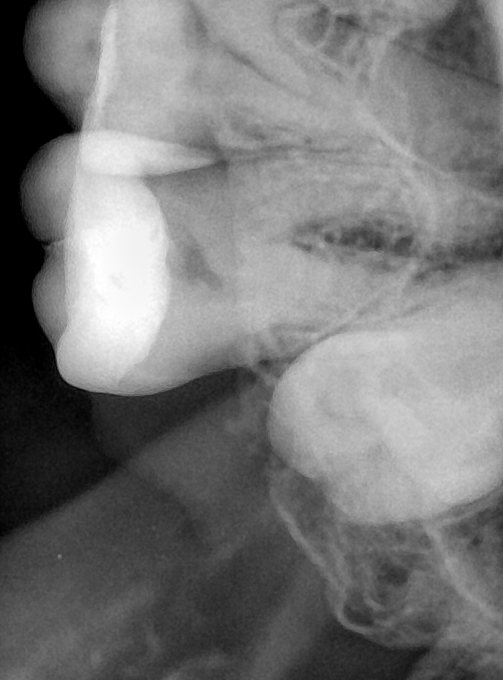

第三版算法分辨率效果比较

Updated: 2026-04-13(更新日期)

| 编号 | 原图 | 第一版 | 第二版 | 第三版 1216x1600 | 第三版 768x1024 | 第三版 1120x1120 |

|---|---|---|---|---|---|---|

| 131315.jpg | ![]() | ![]() | ![]() | ![]() | ![]() | ![]() |

| 131316.jpg | ![]() | ![]() | ![]() | ![]() | ![]() | ![]() |

| 131317.jpg | ![]() | ![]() | ![]() | ![]() | ![]() | ![]() |

| 131318.jpg | ![]() | ![]() | ![]() | ![]() | ![]() | ![]() |

| 131319.jpg | ![]() | ![]() | ![]() | ![]() | ![]() | ![]() |

| 131320.jpg | ![]() | ![]() | ![]() | ![]() | ![]() | ![]() |

| 131321.jpg | ![]() | ![]() | ![]() | ![]() | ![]() | ![]() |

| 131326.jpg | ![]() | ![]() | ![]() | ![]() | ![]() | ![]() |